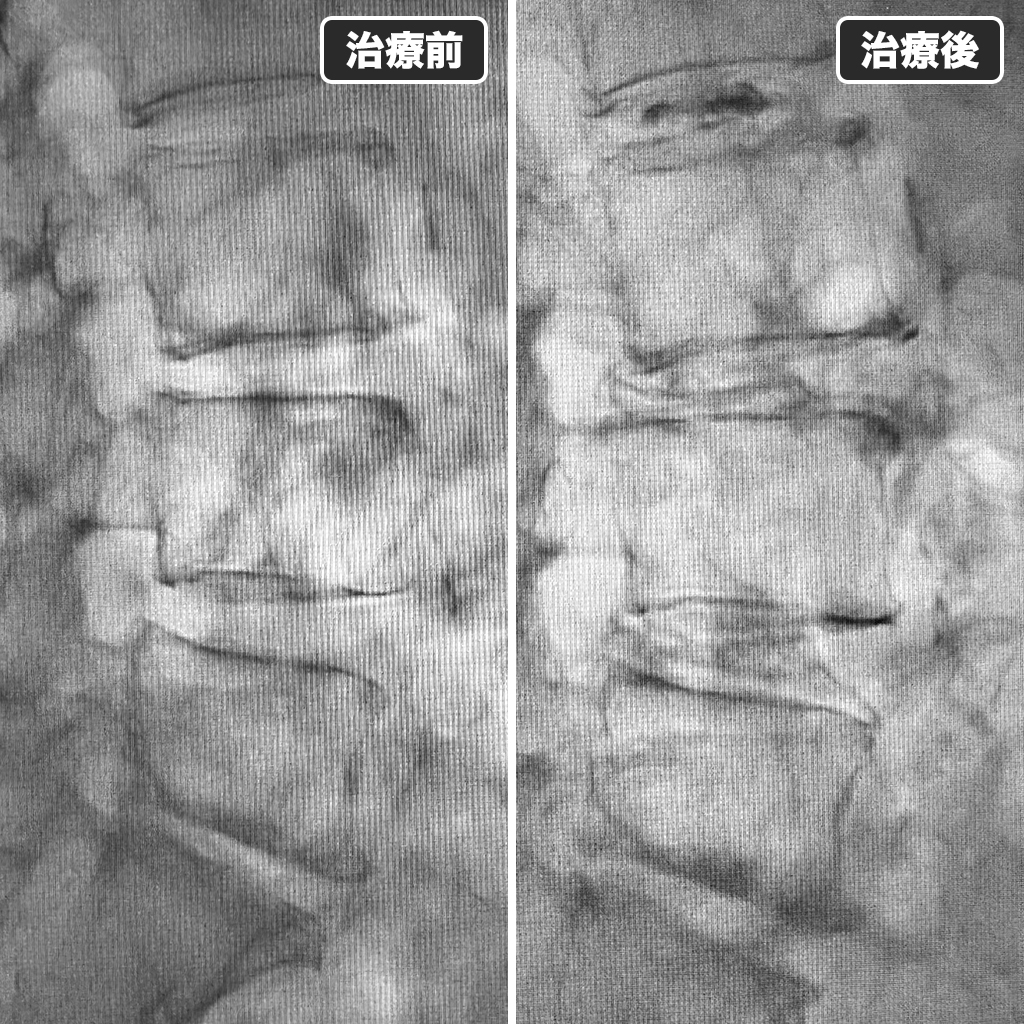

治療前後のレントゲン写真

治療前後のレントゲン写真になります。左側が治療前、右側が治療後になります。ゴルフの再開は1ヵ月後である事をご説明しました